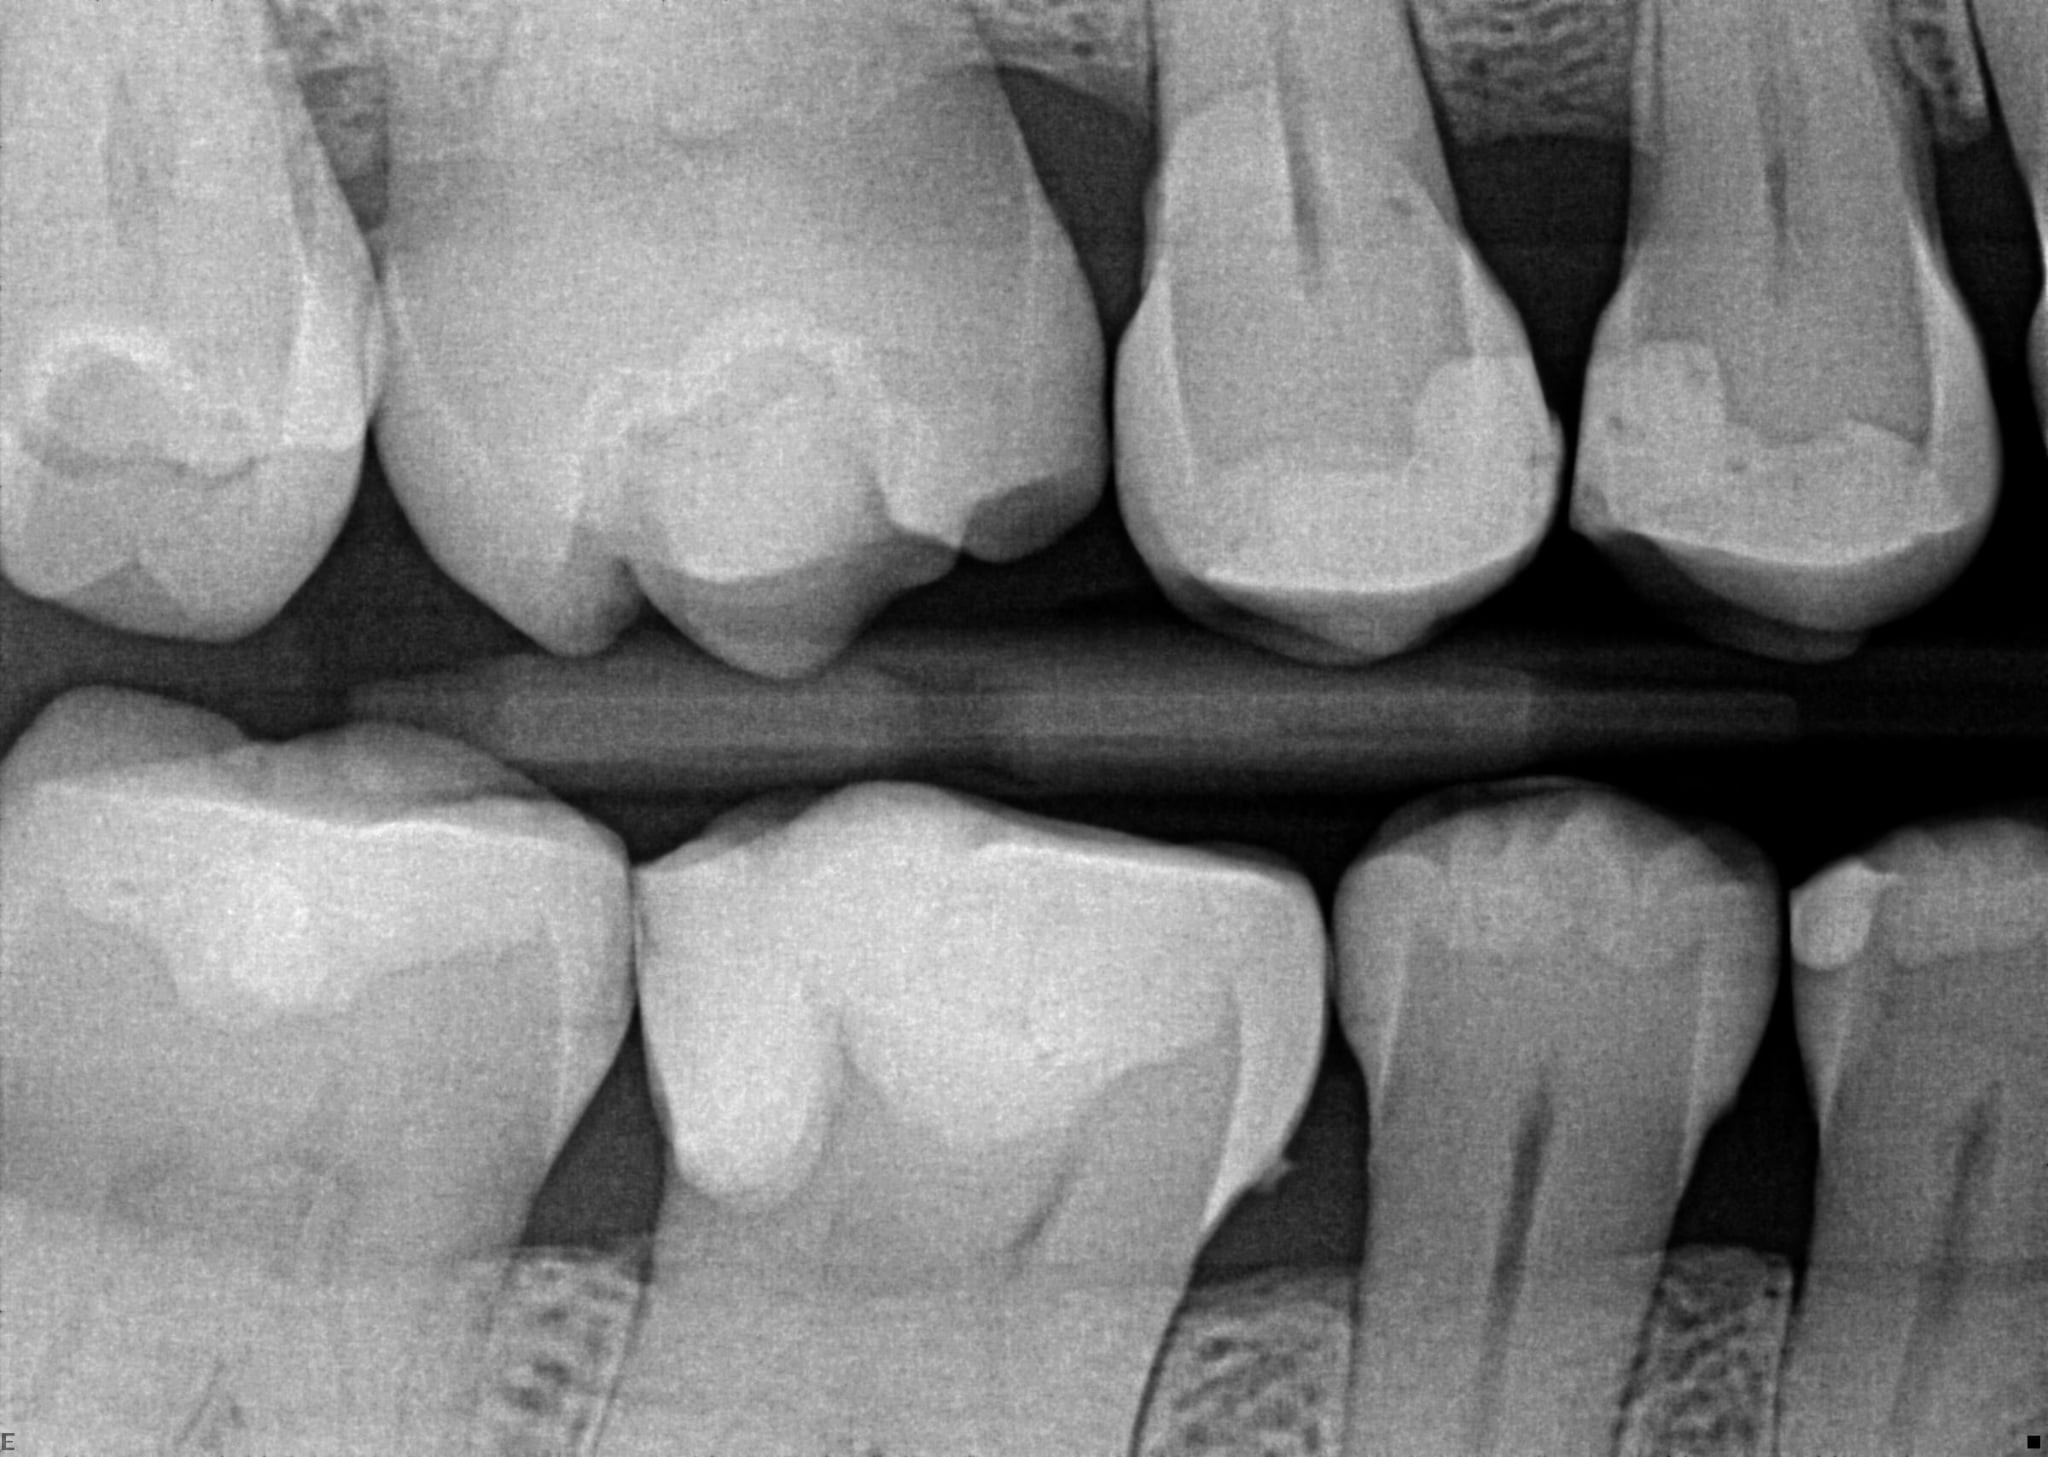

6. On which surface a recurrent caries can be detected?

7 / 35

7. On which surface a recurrent caries can be detected?

No cavity can be detected, restorations on 1.7, 4.6 and 4.7 are porcelain onlays